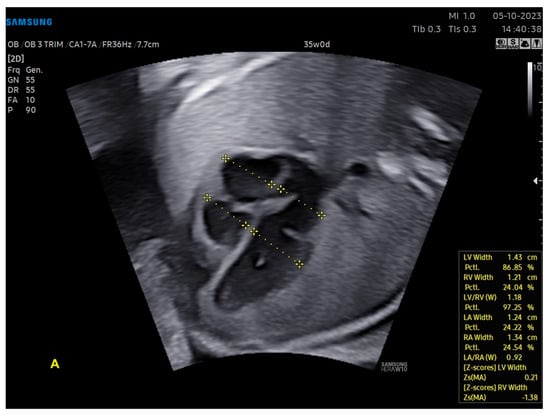

With ML, the ultrasound machine is able to automatically obtain cardiac measurements based on the identification of anatomical cardiac structures, reducing the scan time and inter-observer measurement variation. In this scenario, not only anatomical, but also functional parameters (such as the myocardial performance index) can be automatically measured. With the advances in AI, this technology has been increasingly added to ultrasound devices, such as obstetric ultrasound, and is applicable to three areas: structure identification, automatic measurements, and the classification of diagnosis. AI software (Heart Assist and MPI+—Samsung Healthcare, Gangwon, South Korea) can identify the fetal heart structures and perform automatic biometric and the right and left myocardial performance index measurements, respectively (Figure 12 and Figure 13) [42,43,44].

Figure 12.

Artificial Intelligence (Heart Assistance). The cardiac ultrasound device is able to recognize anatomical heart structures and perform automatic measurements: (A) ventricles (width of atria and ventricles); (B) left ventricular outflow tract (atrioventricular annulus and ascending aorta); (C) aorta in sagittal view (ascending, transverse, isthmus, and descending aortas). Note that the images include the z-scores of these structures, which were also calculated automatically. LV: left ventricle; LA: left atrium; RA: right atrium; RV: right ventricle; Asc. aorta: ascending aorta; Desc. aorta: descending aorta; Transvers. aorta: transverse aorta.